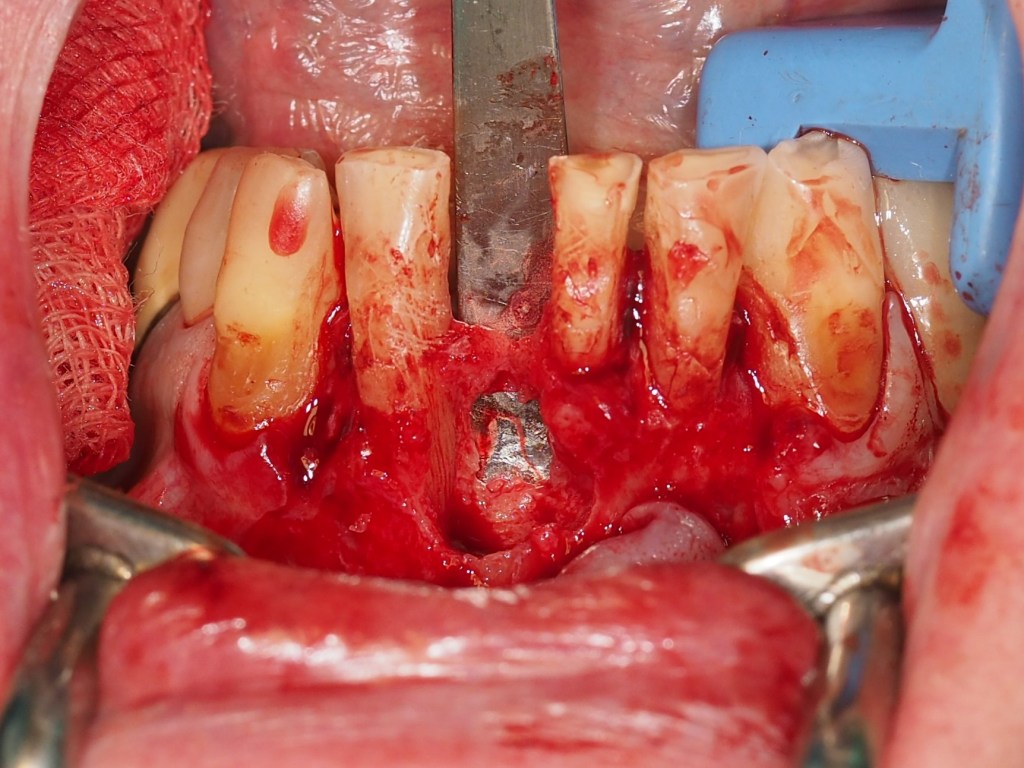

Se decide la extracción del diente 4.1 y la realización de una regeneración ósea guiada mediante el uso de hueso autólogo y membranas reabsorbibles en silla de montar. El diente 3.1 se mantiene de forma estratégica como soporte para una restauración provisional, anticipando su futura extracción en la fase final del tratamiento. En las fotos intraorales de la cirugía, tras la extracción el incisivo y legrado del granuloma, podemos apreciar la ausencia de hueso por vestibular y una perforación en la cortical lingual. (Figuras 9-12).